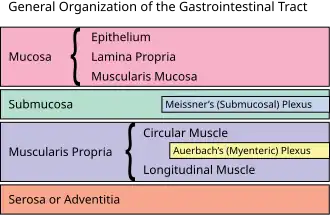

| This article is one of a series on the |

| Gastrointestinal wall |

The submucosal plexus (Meissner's plexus, plexus of the submucosa, plexus submucosus) lies in the submucosa of the intestinal wall. The nerves of this plexus are derived from the myenteric plexus which itself is derived from the plexuses of parasympathetic nerves around the superior mesenteric artery. Branches from the myenteric plexus perforate the circular muscle fibers to form the submucosal plexus. Ganglia from the plexus extend into the muscularis mucosae and also extend into the mucous membrane.

They contain Dogiel cells.[1] The nerve bundles of the submucosal plexus are finer than those of the myenteric plexus. Its function is to innervate cells in the epithelial layer and the smooth muscle of the muscularis mucosae.